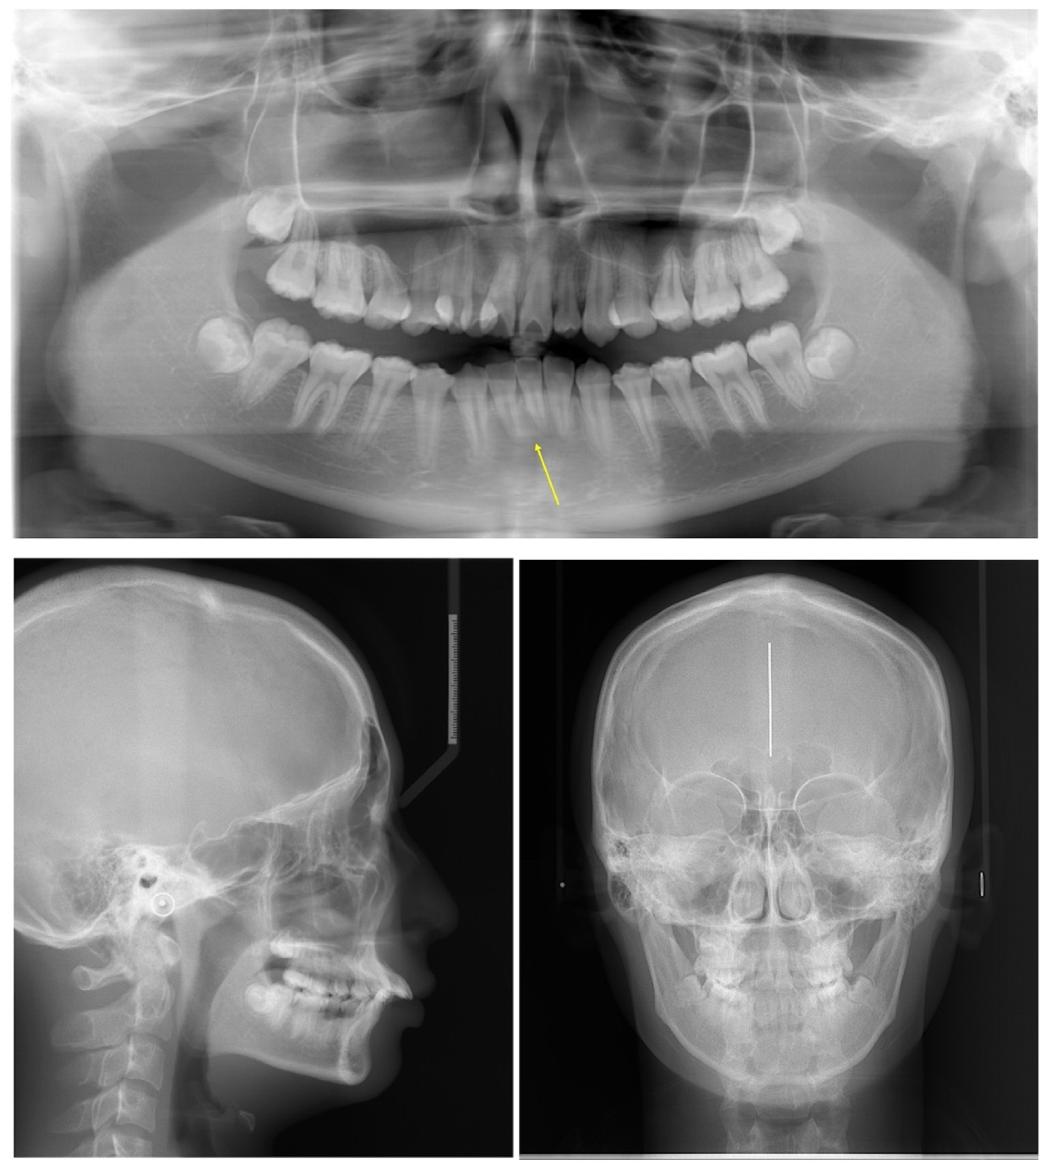

✅ 全景片:牙根平行度良好,牙周组织健康

治疗后X线片显示牙列与骨骼关系优化